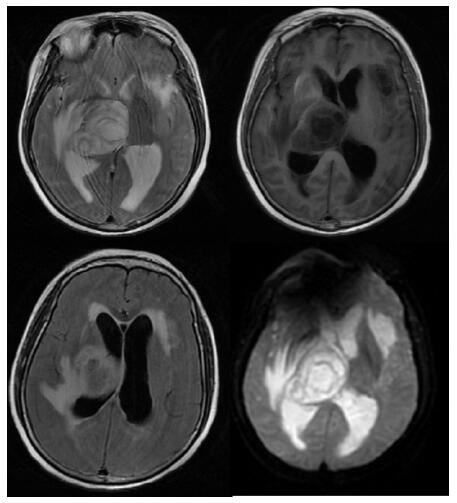

患者,女,54岁,工人,因“头晕5 d”于2019年9月29日至浙江大学附属第二医院急诊就诊。5 d前患者无明显诱因出现头晕,伴行走不稳、四肢乏力,无发热、咳嗽咳痰、胸闷气促、恶心呕吐、四肢抽搐等,未就诊。我院急诊头颅磁共振(MRI)示:右侧丘脑及左侧岛叶异常信号,局部累及右侧中脑(图 1),考虑脑多发占位性疾病。在急诊抢救室予甘露醇100 mL静滴脱水降颅压等对症治疗,5 h后患者逐渐意识模糊。急查血常规:白细胞16.1×109/L,中性粒细胞百分比73.4%;头颅CT示右侧丘脑、左侧岛叶病变,伴脑室扩张(图 2);急诊行“双侧脑室外引流术”,术中引流液呈淡血性。术后诊断:⑴(右侧丘脑)颅内占位性病变,脓肿首先考虑,肿瘤需排除;⑵脑积水;⑶脑疝。患者带气管插管转入ICU进一步治疗。当时体温38.3℃,脉搏99次/min,呼吸频率24次/min,血压169/87 mmHg(1 mmHg= 0.133 kPa),颈软,神志昏迷,右侧瞳孔3 mm,左侧瞳孔2.5 mm,对光反射迟钝。双肺呼吸音粗,可闻及少量啰音。左侧病理征阳性。患者3个月前曾因“反复胸闷气促伴发热1个月余”在本院风湿科住院,当时胸部高分辨CT示两肺间质性肺炎、下叶为著(图 3);血化验示血沉偏高,抗心磷脂抗体阳性;诊断为“间质性肺炎”,住院期间予甲泼尼龙40 mg/d静滴×8 d,60 mg/d静滴×6 d,共住院14 d;出院后予口服甲泼尼龙40 mg/d联合雷公藤多苷片每次20 mg,一日2次治疗;此后规范于本院门诊复诊。本次起病前2个月甲泼尼龙已减量至36 mg/d口服治疗。

| 右侧丘脑及左侧岛叶异常信号,局部累及右侧中脑 图 1 患者2019-09-29头颅MRI平扫+黑水成像 |